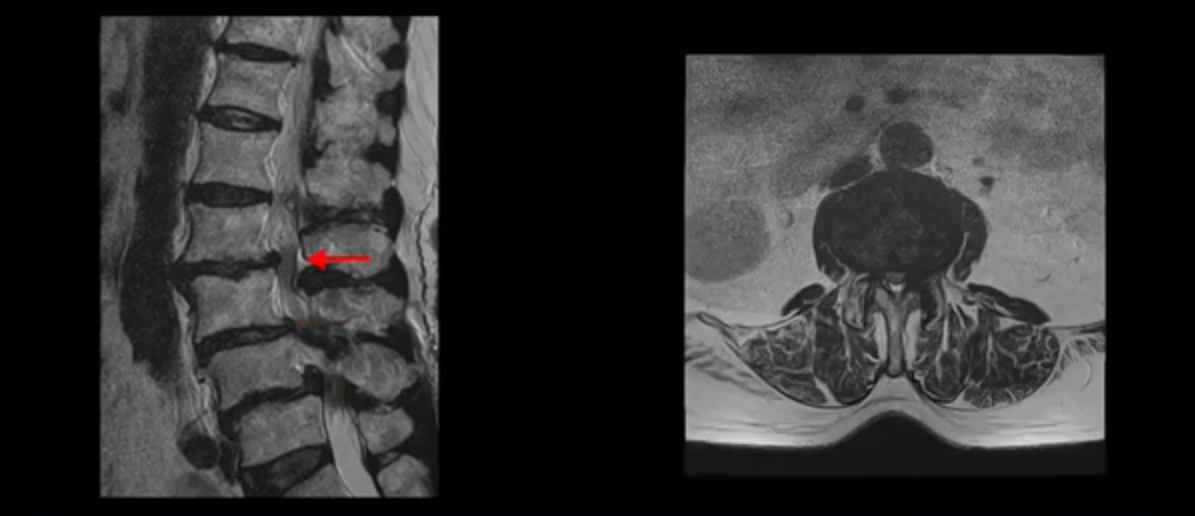

보시다시피 허리 다섯 마디 전부가 다 퇴행되어 있고,

두 마디에 전방전위증이 있고,

4번 5번에 중심성 협착이 심하고

거의 모든 추간공 즉, 신경가지가 좌우로 빠져나가는 구멍이 다 좁아져 있습니다.

척추가 이런 상태니까 양쪽 엉치와 다리가 다 저리고 아프며 지팡이를 짚고 겨우 걷는 상태였습니다. 이렇게 국내 최상위 대학병원에서도 수술하지 말라고, 수술하면 더 안 좋을 거라는 얘기를 들은 고령의 말기 협착증 환자가 근육 재활치료로 좋아질 수 있을까요? 당연히 좋아질 수 있습니다. 무슨 근거로 이렇게 자신있게 얘기하는 걸까요? 왜냐하면 근육이 좋아지는 만큼 협착증 증상이 좋아지기 때문입니다. 근육은 뭉친 걸 반복해서 풀어주고 환자 상태에 맞는 적절한 운동을 잘 하는만큼 좋아질 가능성이 매우 높습니다. 저희는 수많은 치료 후기와 임상시험을 통한 국제학술 논문 등을 통하여 이렇게 여러 마디가 안 좋은 고령의 말기 협착증 환자분들도 근육을 치료하여 근육 상태가 좋아지면 협착증 증상이 좋아진다는 걸 계속해서 보여드리고 있습니다.